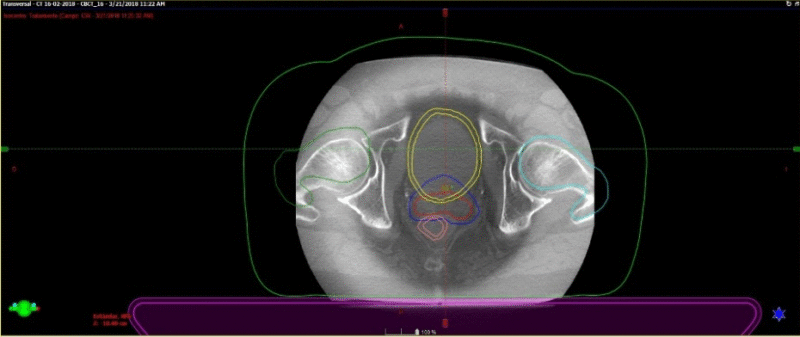

Fig. 3. Técnica de Radioterapia IGRT (Guiada por imágenes). Derecha: TAC de simulación con contornos: Rojo CTV: clinic target volume(próstata y vesículas seminales); Azul: PTV: patologic target volume); Amarillo: Vejiga (OAR); Rosado: Recto (OAR); Verde: Cadera derecha (OAR); Celeste: Cadera izquierda (OAR). Izquierda: Conbeam en máquina de tratamiento, en donde la imagen en el aceleradorse superpone con los contornos hecho en el TAC de simulación.